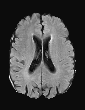

In recent years, data-driven machine learning (ML) methods have revolutionized the computer vision community by providing novel efficient solutions to many unsolved (medical) image analysis problems. However, due to the increasing privacy concerns and data fragmentation on many different sites, existing medical data are not fully utilized, thus limiting the potential of ML. Federated learning (FL) enables multiple parties to collaboratively train a ML model without exchanging local data. However, data heterogeneity (non-IID) among the distributed clients is yet a challenge. To this end, we propose a novel federated method, denoted Federated Disentanglement (FedDis), to disentangle the parameter space into shape and appearance, and only share the shape parameter with the clients. FedDis is based on the assumption that the anatomical structure in brain MRI images is similar across multiple institutions, and sharing the shape knowledge would be beneficial in anomaly detection. In this paper, we leverage healthy brain scans of 623 subjects from multiple sites with real data (OASIS, ADNI) in a privacy-preserving fashion to learn a model of normal anatomy, that allows to segment abnormal structures. We demonstrate a superior performance of FedDis on real pathological databases containing 109 subjects; two publicly available MS Lesions (MSLUB, MSISBI), and an in-house database with MS and Glioblastoma (MSI and GBI). FedDis achieved an average dice performance of 0.38, outperforming the state-of-the-art (SOTA) auto-encoder by 42% and the SOTA federated method by 11%. Further, we illustrate that FedDis learns a shape embedding that is orthogonal to the appearance and consistent under different intensity augmentations.